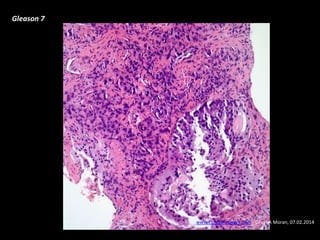

- histology:

- Gleason scores

Prostate cáncer pathology

Adenocarcinoma

Gleason “grade” is from 1-5

based on glandular

architecture

Gleason score is the total

primary grade (1-5) +

secondary grade (1-5) = 2-10

 4-6/10=well-differentiated

 7/10=moderately differentiated

 >8/10=poorly differentiated

Gleason 7

www.cancernetwork.com - Cesar A Moran, 07.02.2014